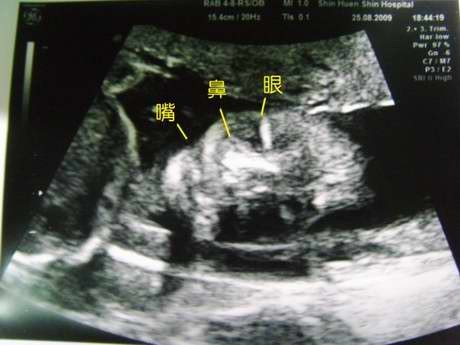

[20W3D]

20W3D,小菜包536克重。

今天可以很清楚的看見小菜包的臉部,

鼻子跟嘴巴中間沒有縫隙,所以是沒有兔唇的...

因為小菜包已經算很大了,超音波的探頭範圍為15公分多,

所以很難拍到全身照,只能拍局部...

*劉醫師在照小菜包的臉,幫我調個好角度拍照,

可以看到小菜包的嘴一張一合的在喝羊水。

*另外檢查了小菜包的各臟器,

心臟、胃、兩個腎臟、膀胱,都一個一個點給我看...

*小菜包很愛踢,所以當然也要照一下他的雙腳,

果然就是這樣踢來踢去,還可以看見兩個可愛的小腳掌喔...^^